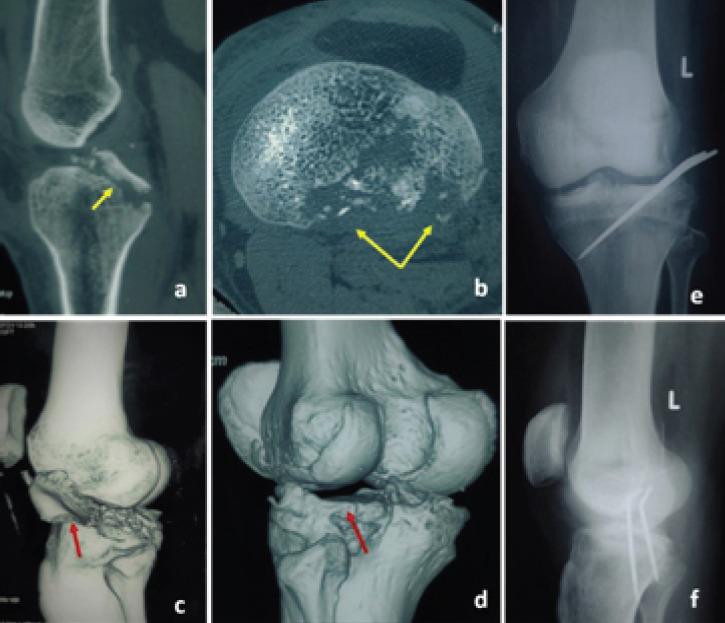

The first and second patients presented primarily to us following fall from motorbikes. Both these patients had injuries of the anterior cruciate ligament (ACL), medial collateral ligament (MCL), lateral meniscus body and posterior root tear, and osteochondral fracture of posterolateral tibia. The osteochondral fracture was managed by internal fixation with headless compression screws. The ligaments were either repaired or reconstructed and meniscus root tear was treated by transtibial pull through repair. The third patient also had the same injury but was treated at another center. He presented with early arthritis of the lateral tibiofemoral joint and valgus malalignment. Treatment for him was in the form of lateral distal femur open-wedge osteotomy and MCL reconstruction. All three patients had good outcome at the end of 1year.

第一例和第二例患者最初是在骑摩托车摔倒后前来我们这里就诊的。这两名患者均有前交叉韧带(ACL)损伤、内侧副韧带(MCL)损伤、外侧半月板体部和后根部撕裂,以及胫骨后外侧骨软骨骨折。骨软骨骨折采用无头加压螺钉内固定治疗。韧带进行了修复或重建,半月板根部撕裂采用经胫骨牵拉缝合修复治疗。第三例患者也有相同的损伤,但在另一家中心接受治疗。他表现为胫股外侧关节早期关节炎和外翻畸形。对他的治疗方式为股骨远端外侧开放楔形截骨术和MCL重建。所有三名患者在1年末均取得了良好的疗效。